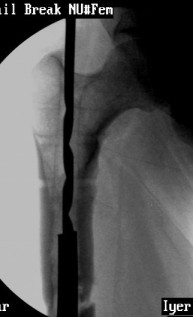

VMI-I am enclosing pictures of how I had to do it once. The C arm picture shows the first attempt to try and jam a solid reamer into the nail and trying to pull it out. Did not work.

The second picture shows a plain guide wire inserted thro the nail, prograde, hammered out thro the distal femur, out thro the skin. A beaded guide wire being railroaded on the earlier G W into the distal end of the nail.